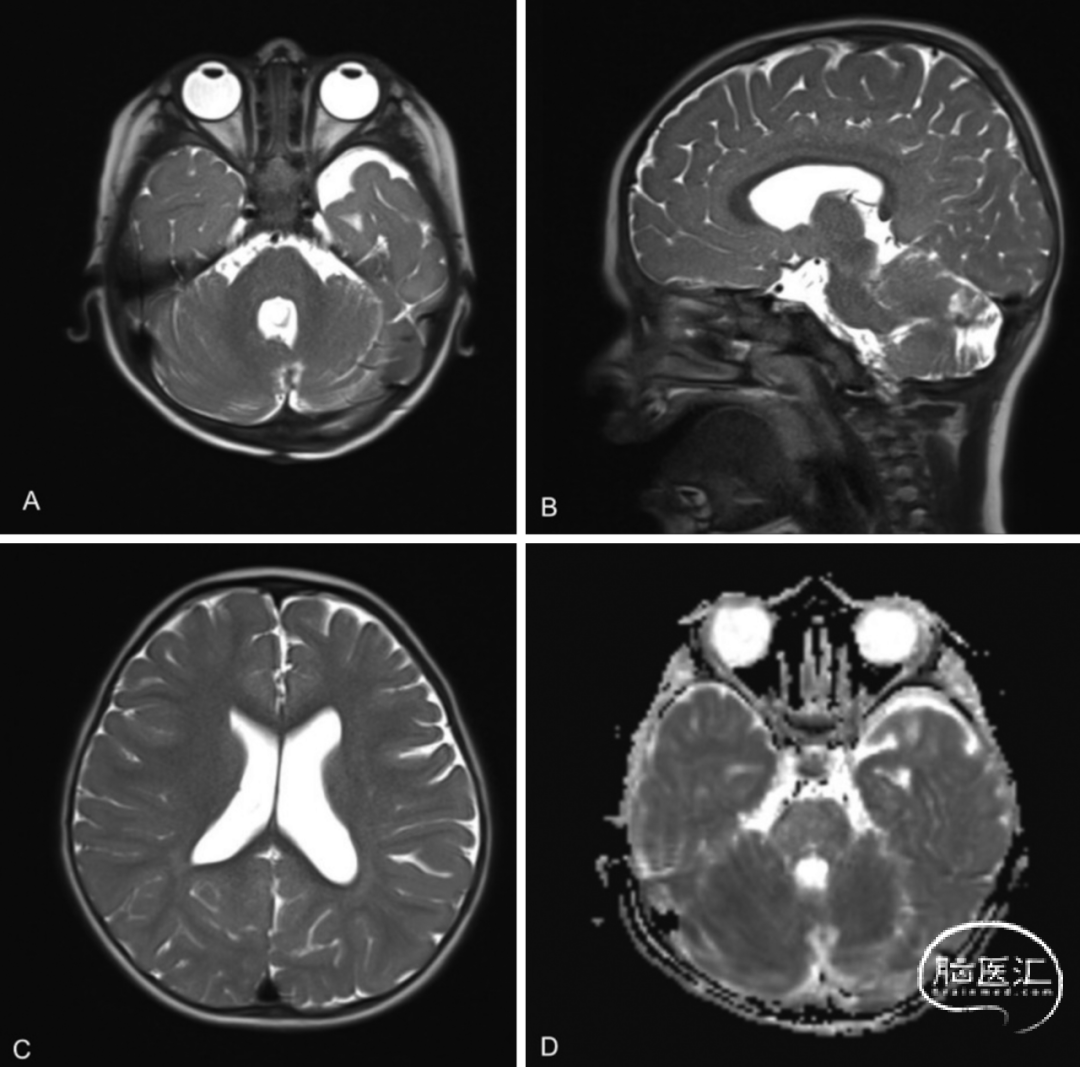

● 术后患者恢复顺利(图4)。给予地塞米松控制水肿。患者出现短暂恶心、呕吐,3天后症状缓解并出院。最终病理报告确认切除的肿块为复发性皮样囊肿,无感染。术后1个月随访时,患者运动功能恢复至术前水平,恢复良好。术后3个月MRI随访显示无残留皮样囊肿,梗阻性脑积水完全缓解(图5)。

图4. 术后MRI检查显示皮样囊肿已完全切除,脑室扩大情况得到部分即刻缓解,与术前相比弥散受限减轻。